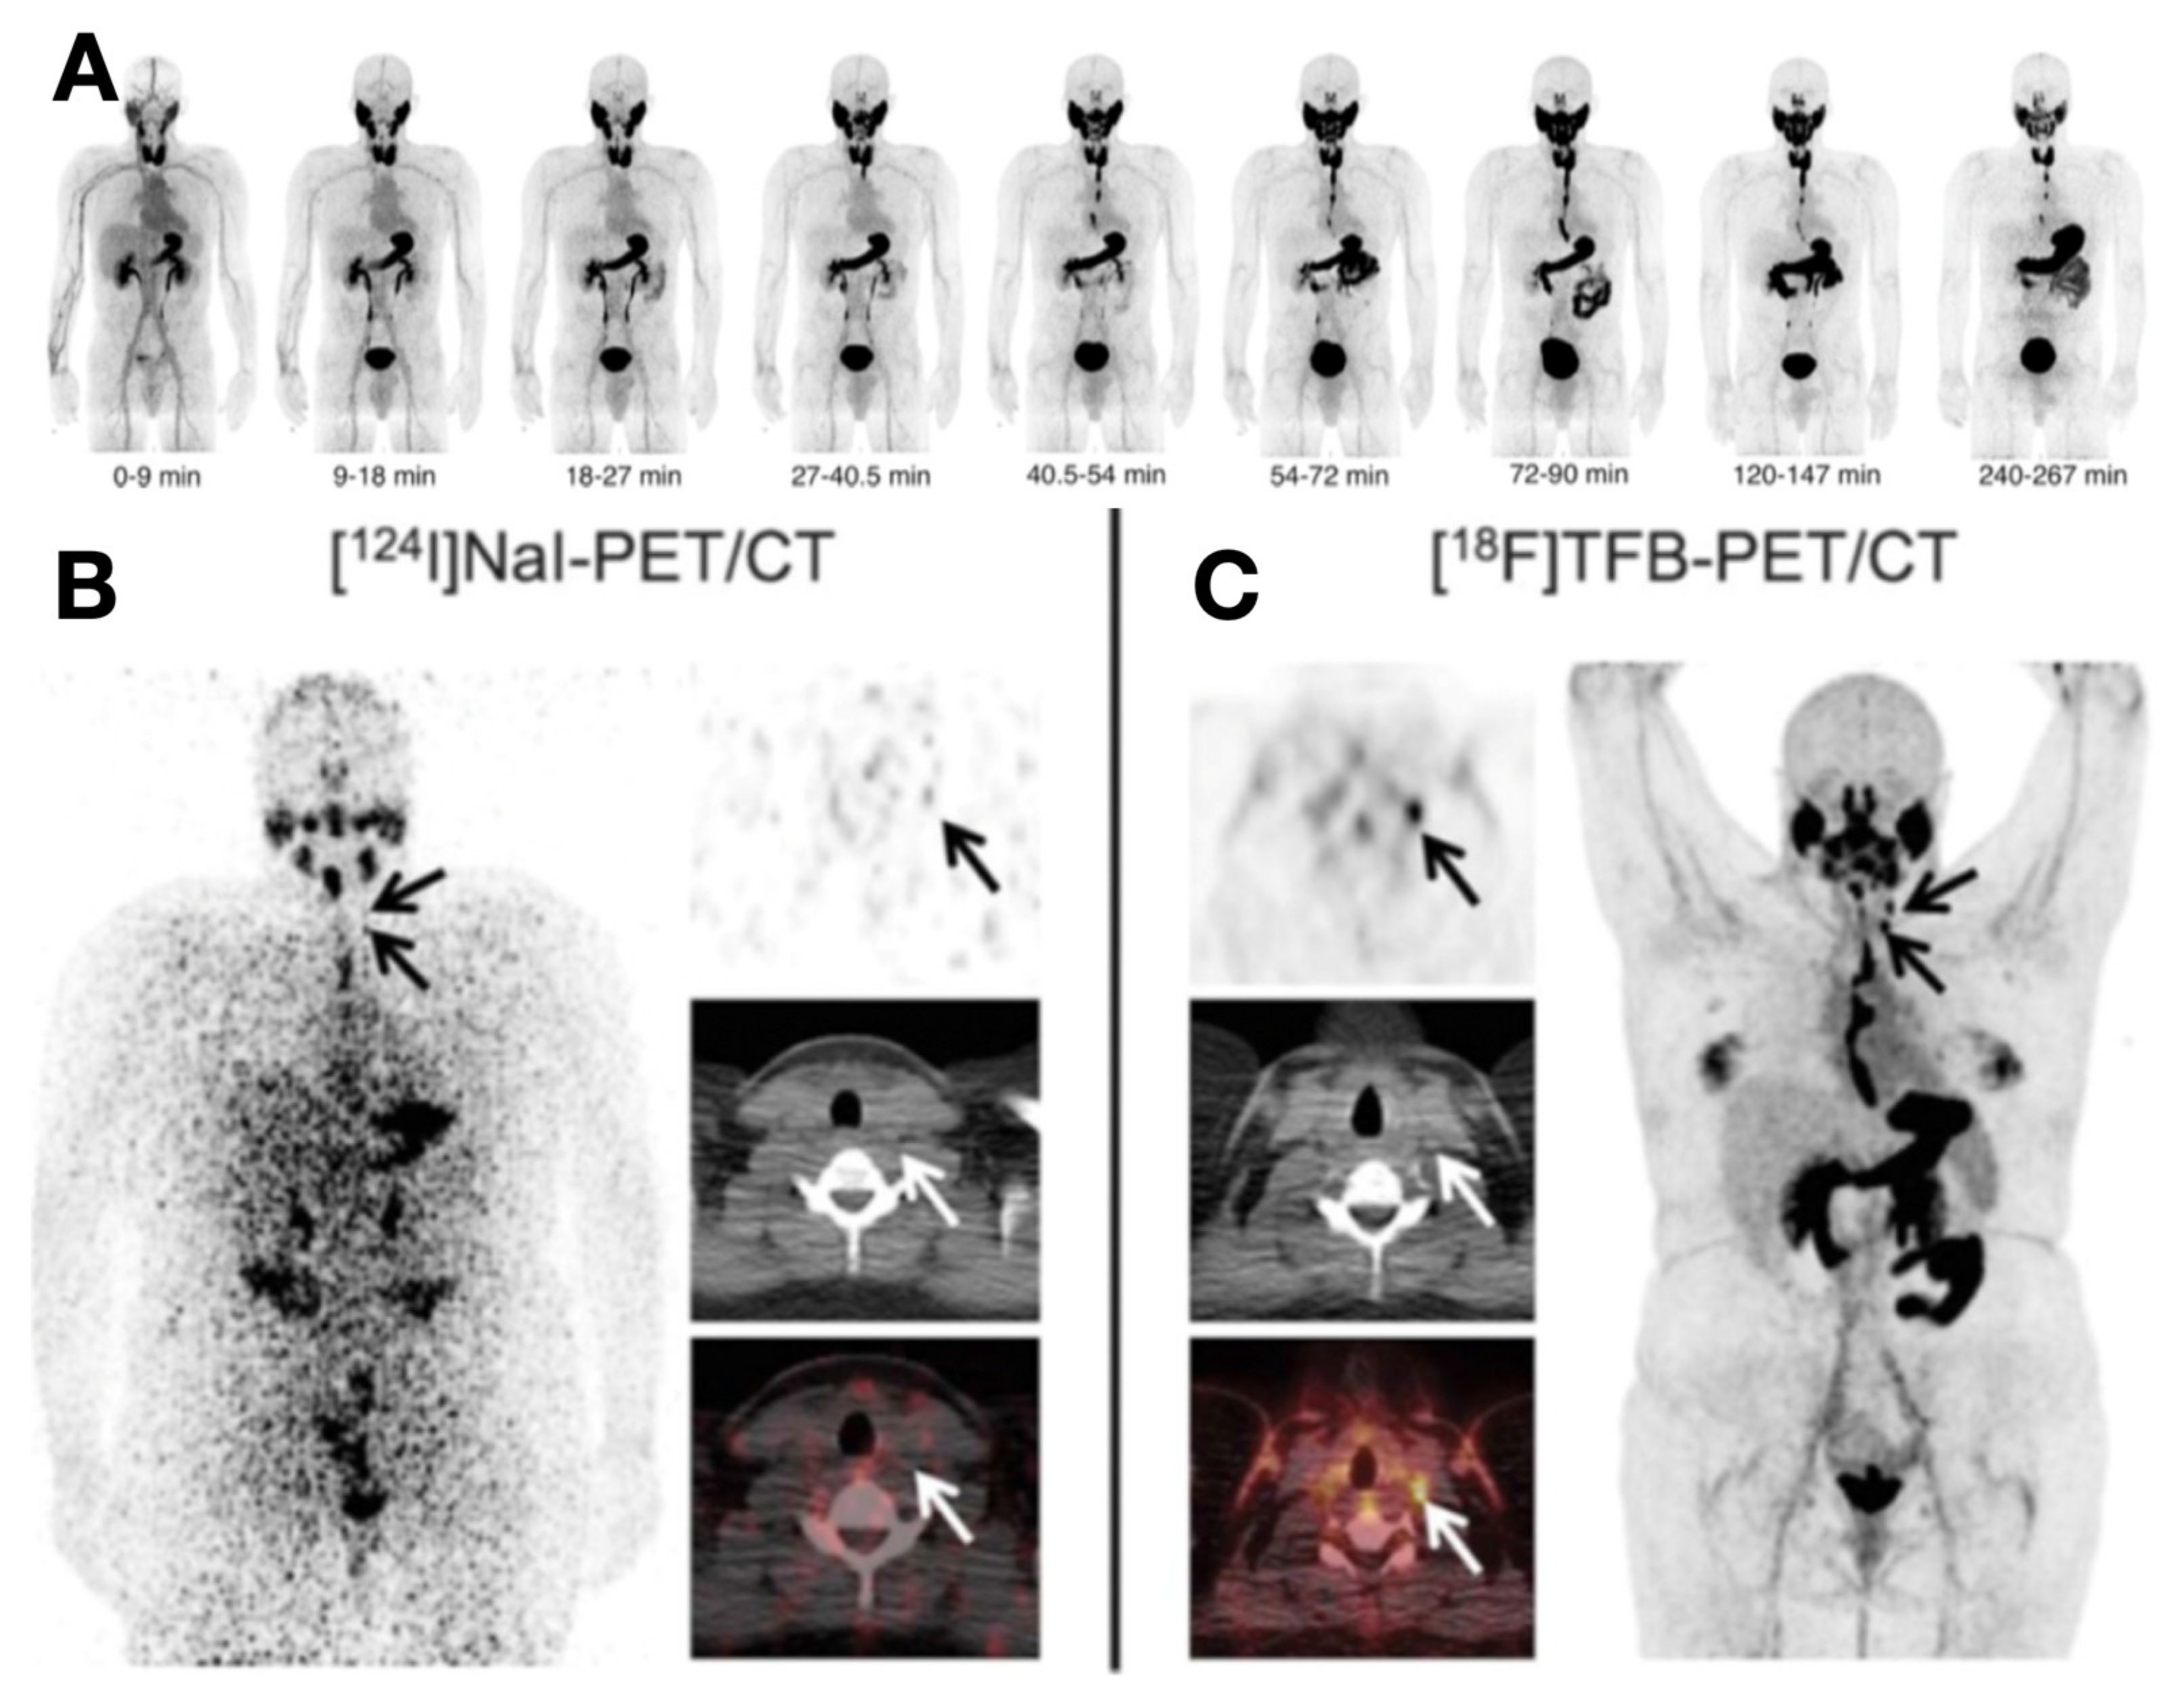

- Samnick, S.; Al-Momani, E.; Schmid, J.-S.; Mottok, A.; Buck, A.K.; Lapa, C. Initial Clinical Investigation of [18F]Tetrafluoroborate PET/CT in Comparison to [124I]Iodine PET/CT for Imaging Thyroid Cancer. Clin. Nucl. Med. 2018, 43, 162–167. [Google Scholar] [CrossRef]